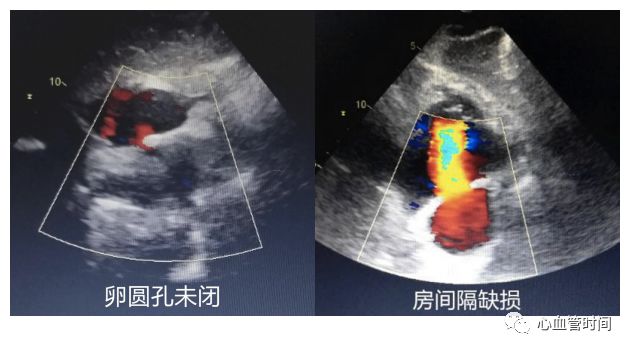

剑突下切面

对于一些胸前切面显示不清的患者,剑突下切面可以很好地 作以补充。 房间隔 在患者成像条件良好的前提下,剑突下切面是观察 房间隔缺损的绝佳切面。该切面房间隔相对垂直于探头,可更好的显示 过隔血流,像卵圆孔未闭的几毫米的血流也能轻松显示,且可更好的与腔静脉的血流做区分,明确血流来源。 下腔静脉

房间隔观察有无过隔血流、膨出瘤及摆动现象。一定要注意区分右房内的

红色血流是起源自下腔静脉还是房间隔,避免误诊。

三尖瓣观察三尖瓣形态及反流情况。

房间隔观察有无过隔血流、膨出瘤及摆动现象。一定要注意区分右房内的

红色血流是起源自下腔静脉还是房间隔,避免误诊。

房间隔当存在

房间隔缺损时,过隔血流因几乎垂直于探头而不易观察,建议可稍微

偏转探头调整血流角度进行观察。

室壁观察室壁形态及运动情况。

房间隔当存在

房间隔缺损时,过隔血流因几乎垂直于探头而不易观察,建议可稍微

偏转探头调整血流角度进行观察。